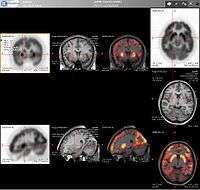

- Neurology: PET neuroimaging is based on an assumption that areas of high radioactivity are associated with brain activity. What is actually measured indirectly is the flow of blood to different parts of the brain, which is, in general, believed to be correlated, and has been measured using the tracer oxygen-15. However, because of its 2-minute half-life, O-15 must be piped directly from a medical cyclotron for such uses, which is difficult. In practice, since the brain is normally a rapid user of glucose, and since brain pathologies such as Alzheimer's disease greatly decrease brain metabolism of both glucose and oxygen in tandem, standard FDG-PET of the brain, which measures regional glucose use, may also be successfully used to differentiate Alzheimer's disease from other dementing processes, and also to make early diagnosis of Alzheimer's disease. The advantage of FDG-PET for these uses is its much wider availability. PET imaging with FDG can also be used for localization of seizure focus: A seizure focus will appear as hypometabolic during an interictal scan. Several radiotracers (i.e. radioligands) have been developed for PET that are ligands for specific neuroreceptor subtypes such as [11C] raclopride, [18F] fallypride and [18F] desmethoxyfallypride for dopamine D2/D3 receptors, [11C] McN 5652 and [11C] DASB for serotonin transporters, [18F] Mefway for serotonin 5HT1A receptors, [18F] Nifene for nicotinic acetylcholine receptors or enzyme substrates (e.g. 6-FDOPA for the AADC enzyme). These agents permit the visualization of neuroreceptor pools in the context of a plurality of neuropsychiatric and neurologic illnesses.

PET scan of the human brain.

The development of a number of novel probes for noninvasive, in vivo PET imaging of neuroaggregate in human brain has brought amyloid imaging to the doorstep of clinical use. The earliest amyloid imaging probes included 2-(1-{6-[(2-[18F]fluoroethyl)(methyl)amino]-2-naphthyl}ethylidene)malononitrile ([18F]FDDNP)[9] developed at the University of California, Los Angeles and N-methyl-[11C]2-(4'-methylaminophenyl)-6-hydroxybenzothiazole[10] (termed Pittsburgh compound B) developed at the University of Pittsburgh. These amyloid imaging probes permit the visualization of amyloid plaques in the brains of Alzheimer's patients and could assist clinicians in making a positive clinical diagnosis of AD pre-mortem and aid in the development of novel anti-amyloid therapies. [11C]PMP (N-[11C]methylpiperidin-4-yl propionate) is a novel radiopharmaceutical used in PET imaging to determine the activity of the acetylcholinergic neurotransmitter system by acting as a substrate for acetylcholinesterase. Post-mortem examination of AD patients have shown decreased levels of acetylcholinesterase. [11C]PMP is used to map the acetylcholinesterase activity in the brain, which could allow for pre-mortem diagnosis of AD and help to monitor AD treatments.[11] Avid Radiopharmaceuticals of Philadelphia has developed a compound called 18F-AV-45 that uses the longer-lasting radionuclide fluorine-18 to detect amyloid plaques using PET scans.[12]